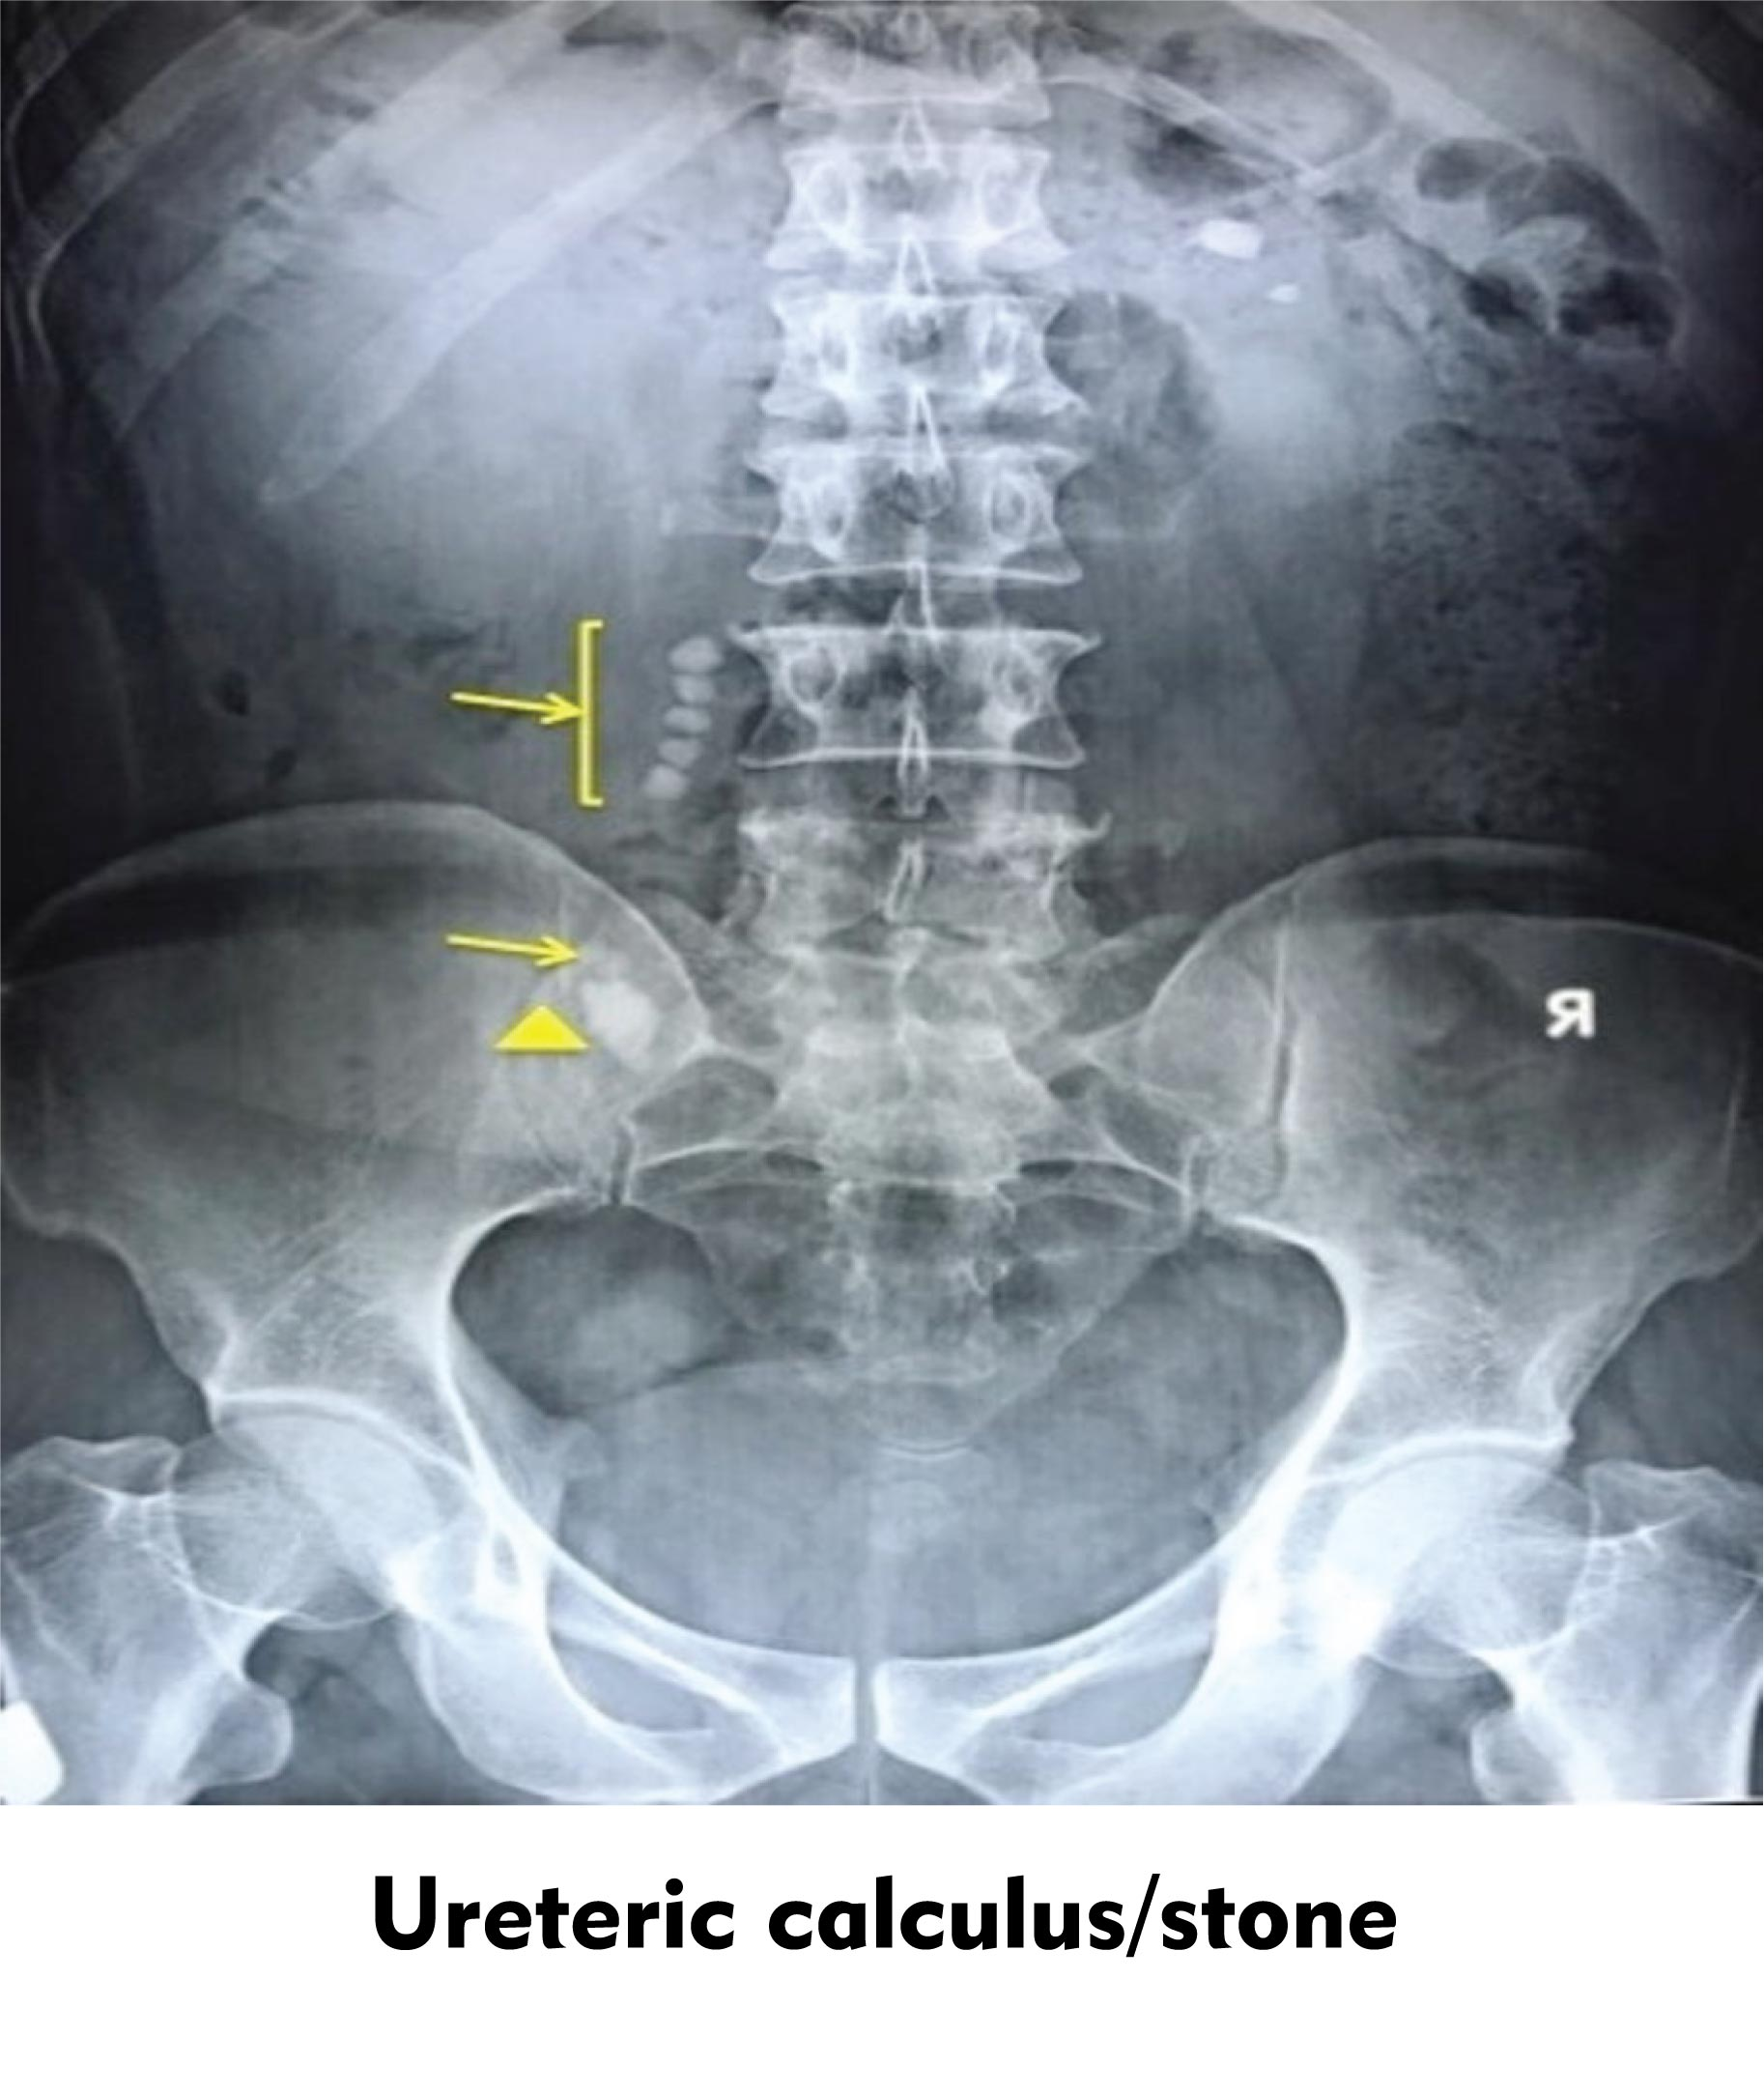

An X-ray of the lower abdomen shows a shade in the region of ureter suspected to be a ureteric calculus. Possible clinical symptoms would be

The possible clinical symptoms of ureteric calculus would be anuria and hematuria. ‘Calculus’ is a concretion of material like mineral salts. It usually forms within an organ or a duct of the body. The condition of the formation of calculus is called ‘lithiasis.’ Thus, stones possess the potential of causing a number of medical conditions.

So, the correct answer is, ‘anuria and hematuria.’